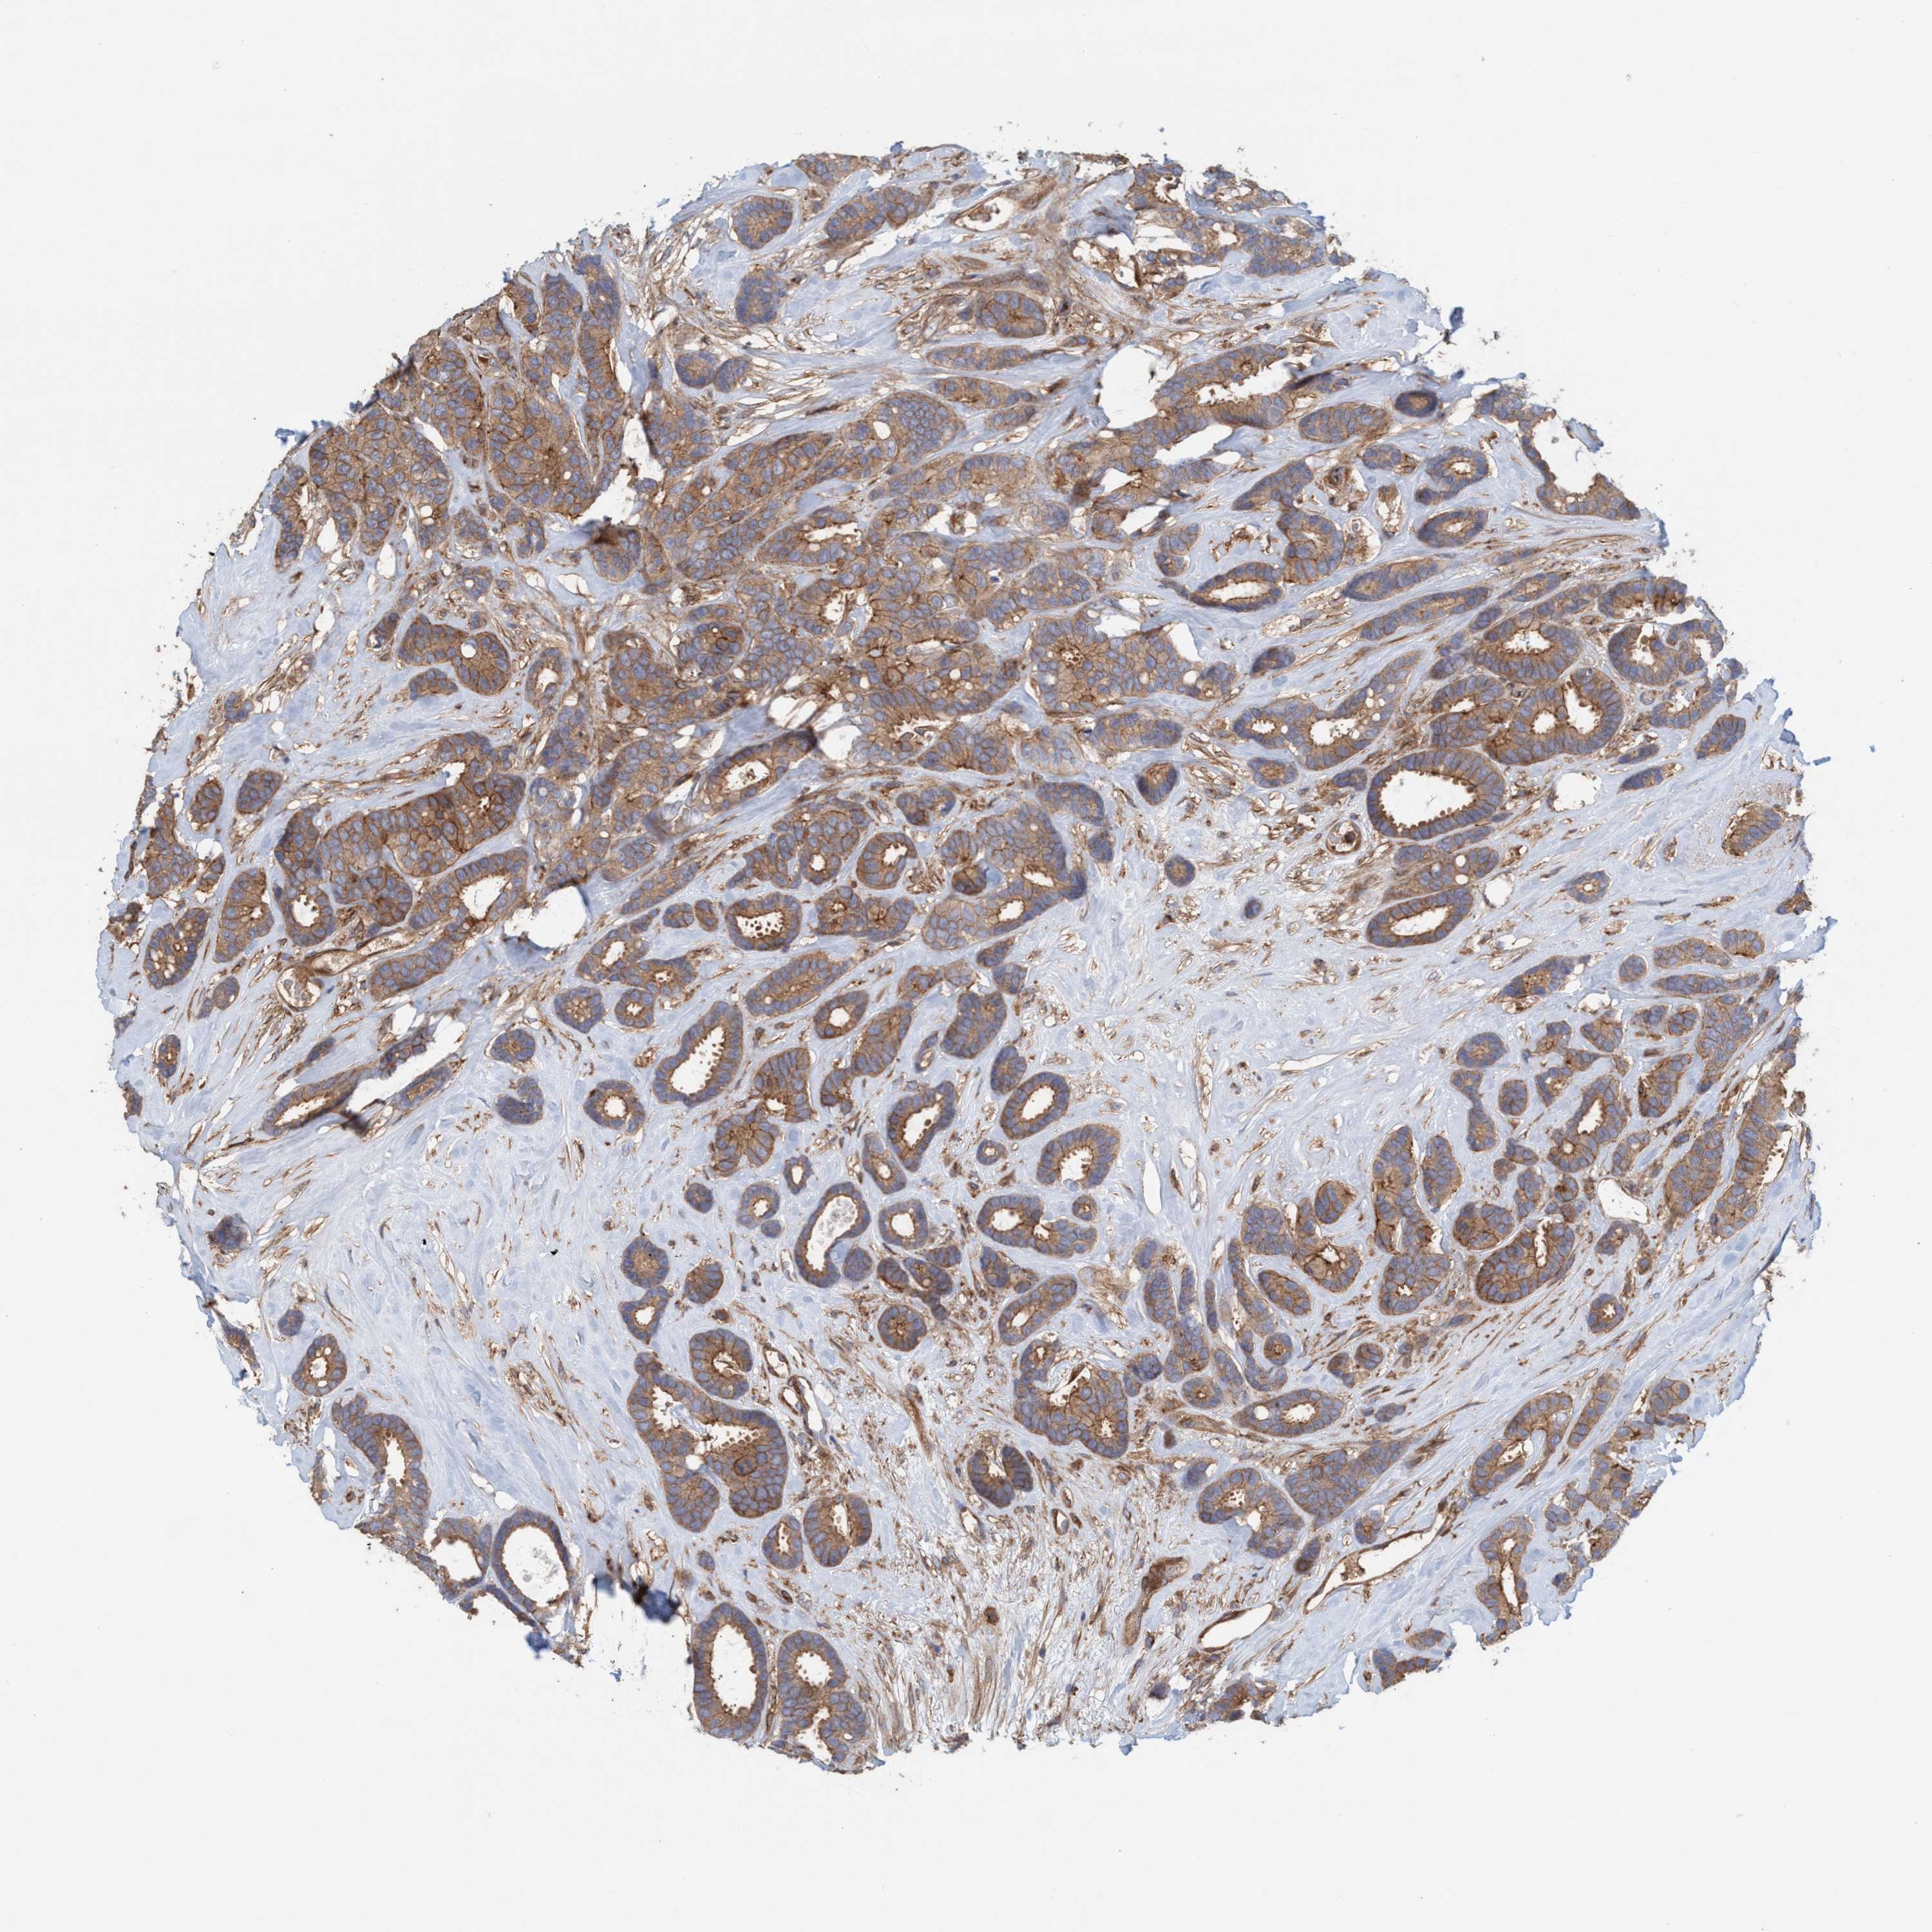

CANCER BREAST CANCER Show tissue menu

BRCA TCGA BRCA VALIDATION PROTEIN EXPRESSION